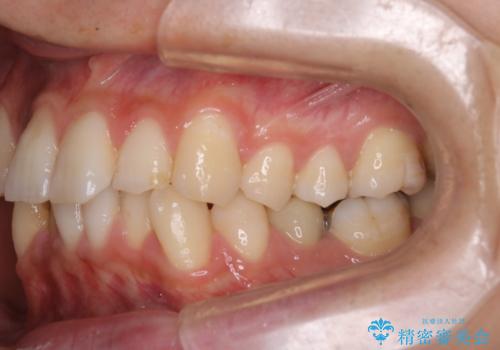

前歯のガタガタを治したい。

- 凸凹を治したいと来院された患者様です。

インビザラインにて、遠心移動を行いながら綺麗に配列することができました。

側切歯が低位の場合、反対咬合を改善した後に挺出させるのはワイヤーの方が適しています。